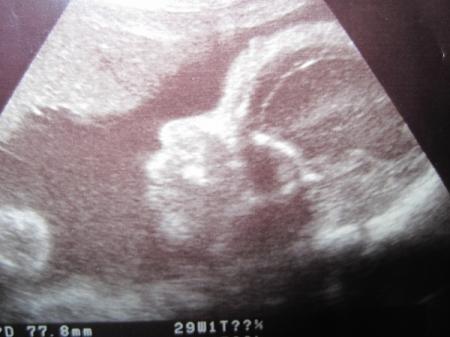

einmal Bauchmaus ;-)

Bild zu